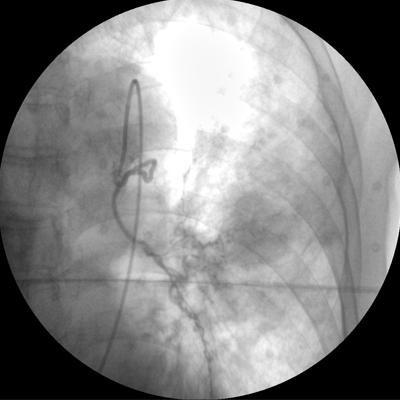

四維電動(dòng)運(yùn)動(dòng)控制,平滑定位,使得復(fù)雜角度快速實(shí)現(xiàn)。

專(zhuān)業(yè)的圖像處理系統(tǒng),為您提供高分辨率、高灰階圖像。